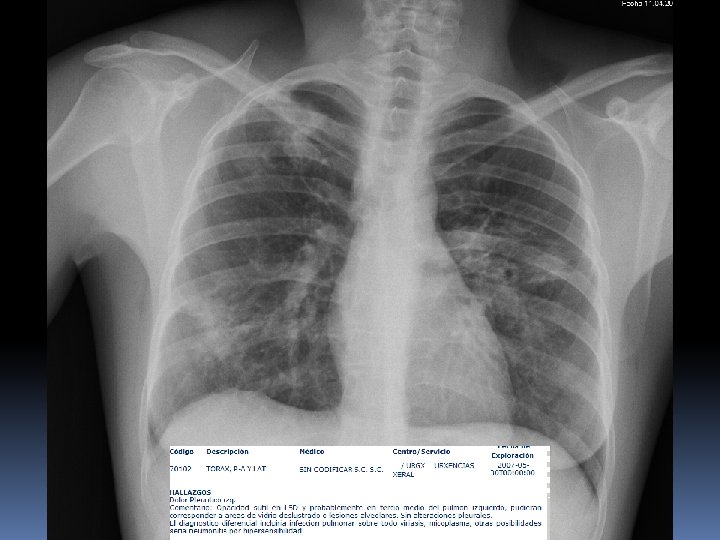

5 años mas tarde……….

2008 2013

Desde AP: Laboratorio: puede haber anemia, linfopenia, eosinofilia, trombocitopenia, hipergammaglobulinemia, aumento de VSG, hipercalcemia e hipercalciuria, alteraciones específicas de órganos afectados. En 50 -80% de pacientes se detecta un aumento de la enzima conversora de angiotensina (secretada por fagocitos del granuloma), lo que indica un estadio activo. Hacer serologías para posibles diagnósticos diferenciales. Radiografía de tórax: el 90 -95% de los pacientes tiene alguna alteración radiológica en tórax; lo más frecuente es observar un patrón intersticial retículo-nodular y/o adenopatías hiliares bilaterales. Otros hallazgos posibles son: calcificaciones hiliares “en cáscara de huevo”, cavitación, bronquiectasias, derrame pleural unilateral (exudado linfocitario), cardiomegalia, hipertensión pulmonar. En caso de eritema nodoso con radiología normal y etiología no filiada es conveniente repetir el estudio radiológico al mes.